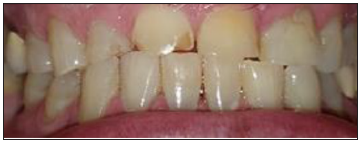

Radiograph and intraoral examinations reveal worn-down teeth [#s 07, 08 and 09] (Figures 1-5) as well as tooth gemination [# 10] (Figures 1-7). The evaluation of periapical radiographs taken of teeth [#s 07, 08, 09, and 10] presents with no evidence of periapical radiolucency. Tooth [# 08], however, shows significant internal root resorption to the mid-way and calcified the apical half of the root to the apex. Tooth [# 09] also shows a significant external/internal root resorption which is more evident on the distal aspect of the tooth, (Figure 7). Both merged segments of geminated tooth [#10] (Figure 6), shows almost completely calcified root canals to the apex. This calcification is also evident in tooth [# 07] (Figure 7).

Figure 2: Facial / Labial view oversized crown of geminated tooth # 10 end to end incisal contacts with chipped incisal edges of anterior teeth.